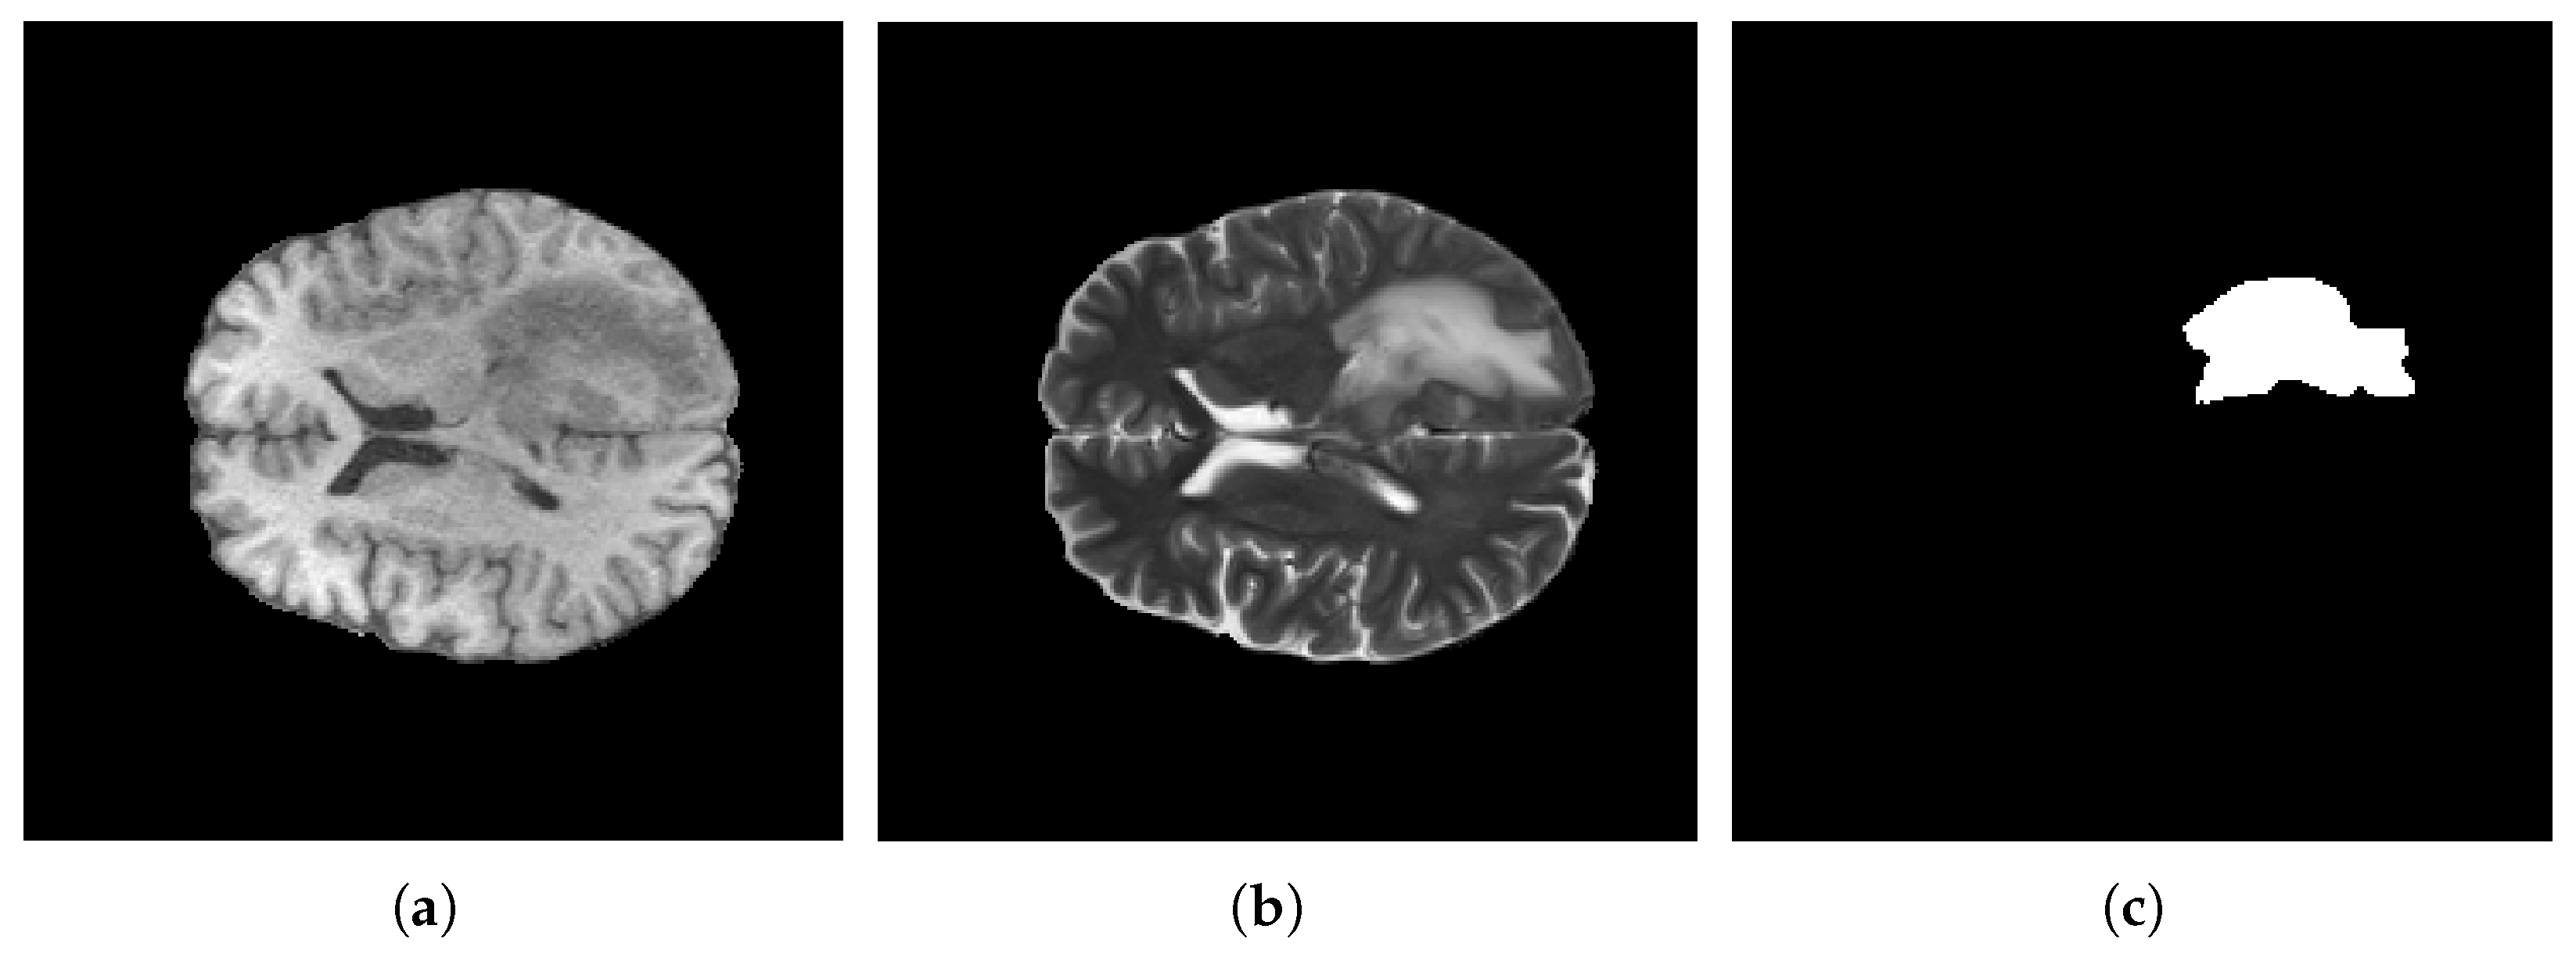

4.3. Data Prepossessing

5.3. Segmentation Results